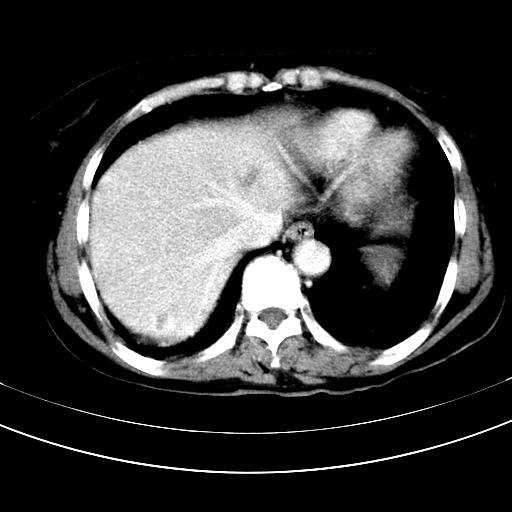

补充强化片

肝左叶及尾叶低密度灶,增强有渐进性明显强化,考虑血管瘤。胃内“充缺”首先要排除异物(食物),变换体位可鉴别。增强时机抓的不好,还应该有延时像。

谢谢楼主的增强片子,平扫没发现左侧肾上腺的问题很不好意思,可惜片子只有门脉期,所以还只有猜,肝脏的病灶在门脉期部分强化,首先考虑为血管瘤(其他的用一种病不好解释)胃要喝水就好了现在不好说是否有问题,左肾上腺的问题考虑是肿瘤。

做了增强后,可以明确胃是没有肿瘤的,肾上腺也没有肿瘤.肝左叶的病灶首先考虑血管瘤,应该再延迟,肝尾状叶的病灶仍不能排除肝癌的可能性.